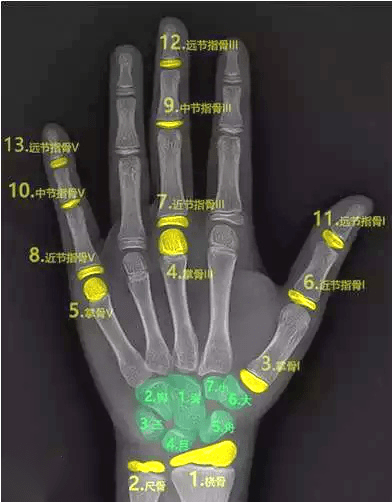

三、骨齡測試法

骨齡是骨骼年齡的簡稱,比實際年齡更能反映人體骨骼的成熟度。

一般是拍攝左手腕部的X線片,觀察指骨、腕骨、橈骨、尺骨下端的骨化中心出現(xiàn)的時間、面積大小、判斷骨骼實際發(fā)育程度,來確定骨齡。

如果骨齡小于生活年齡1歲以上,提示有生長激素缺乏癥的可能;骨齡大于生活年齡1歲以上的孩子可能早熟,往往其成年的最終身高反而受損。

因此骨齡異常需要盡早到專業(yè)醫(yī)療機構(gòu)就診,必要時進行醫(yī)學(xué)干預(yù)和藥物治療。